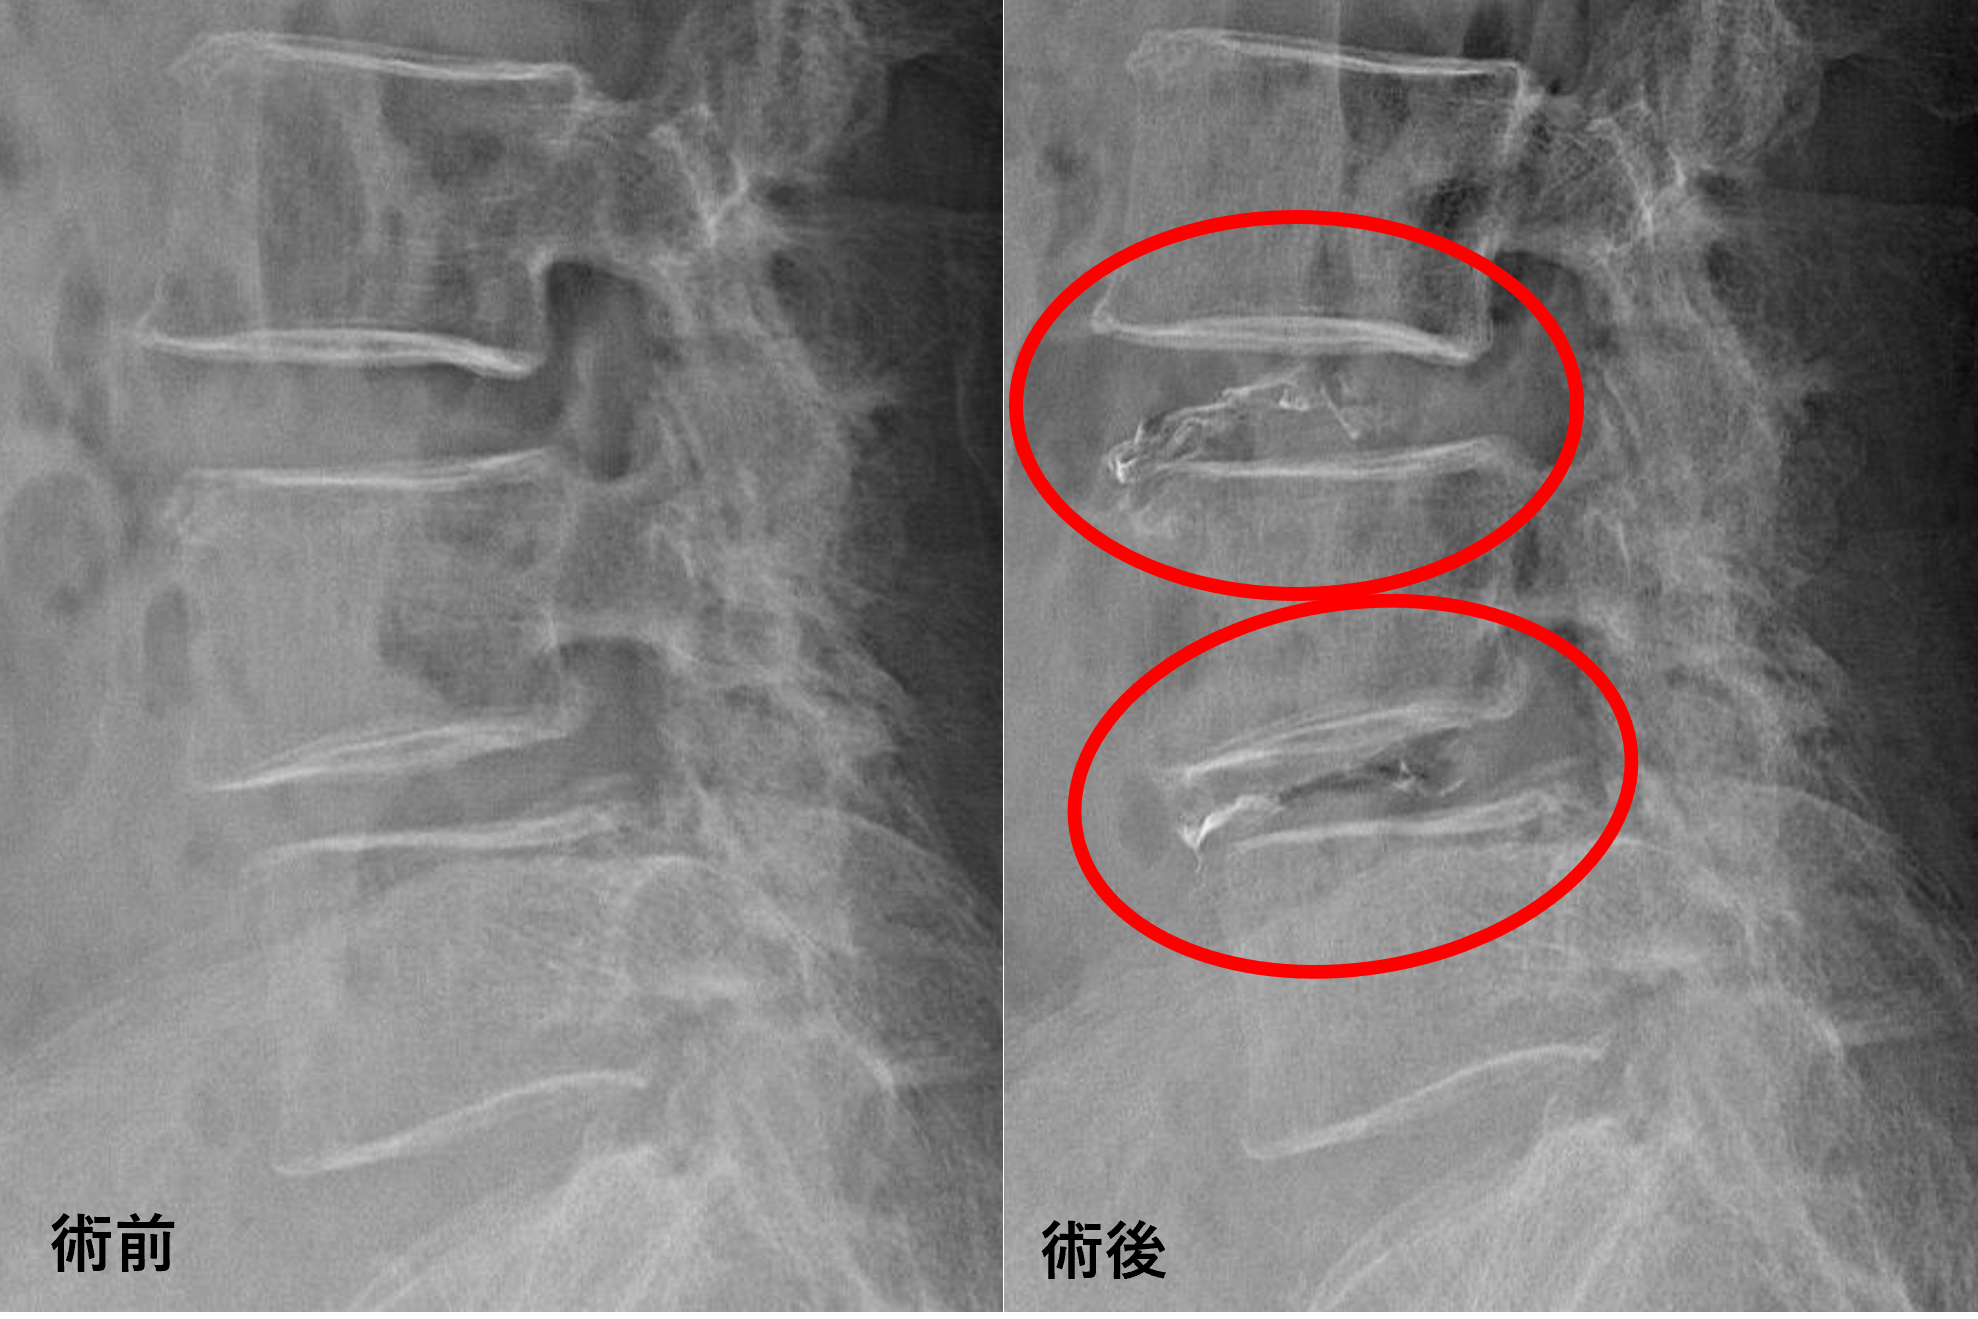

画像及び所見について

- L3/4 – 椎間板変性、椎間板ヘルニア、脊柱管狭窄

- L4/5 – 椎間板変性、膨隆、脊柱管狭窄

以上のことが画像上認められました。

L3/4、4/5の椎間板所見による脊柱管の圧排が、症状の原因の可能性が高い。

患者様と相談の元、L3/4、4/5にセルゲル法を施行